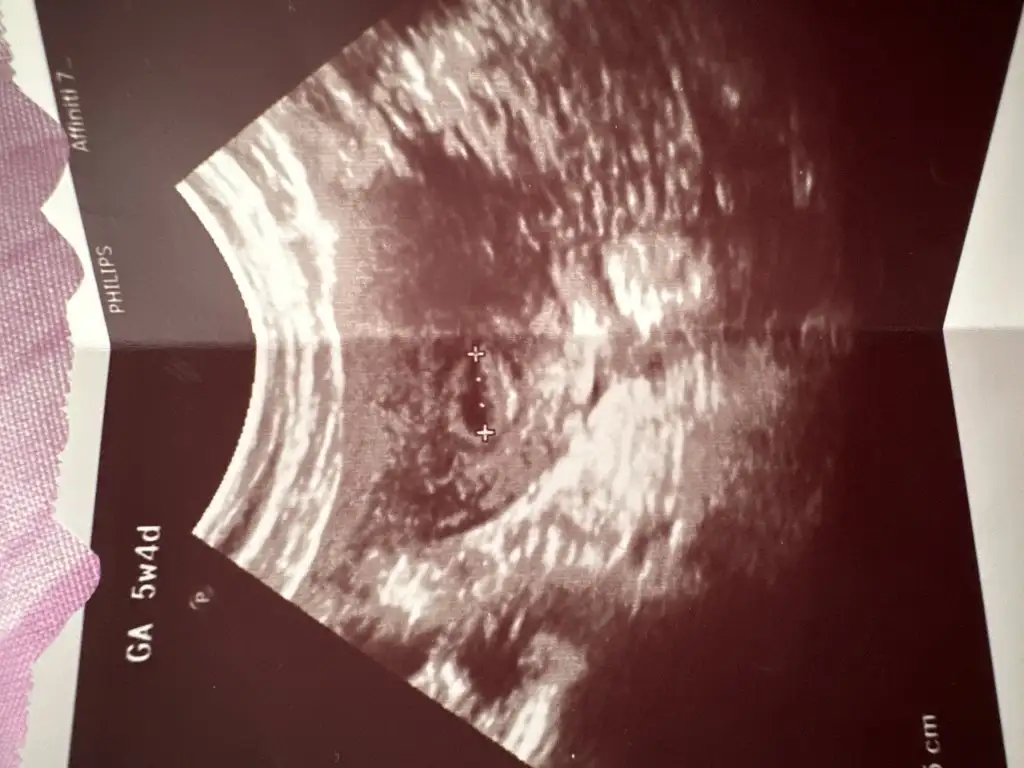

Burada kaç haftalık hamilesiniz bana da iki hafta sonra gel demişti bundan on gün önce de doktora gitmişti başka bir özel hastaneye kesme alttan muayene ederek bakmıştı çok zor görmüştü var ama kesin bir şey söyleyemem demişti beta 1400 olmasına rağmen Sonra devlet hastanesine gittim muhteşem büyümüştü onun resmini atayım size

Evet aynen oyle oluyor 5+6mis burda nereeyse 6 iste sonra bir hafta veya 2 hafta sonra bende gittim ve dedigin gibi muhtesem buyuyor bende sasirmistim baya buyumustu